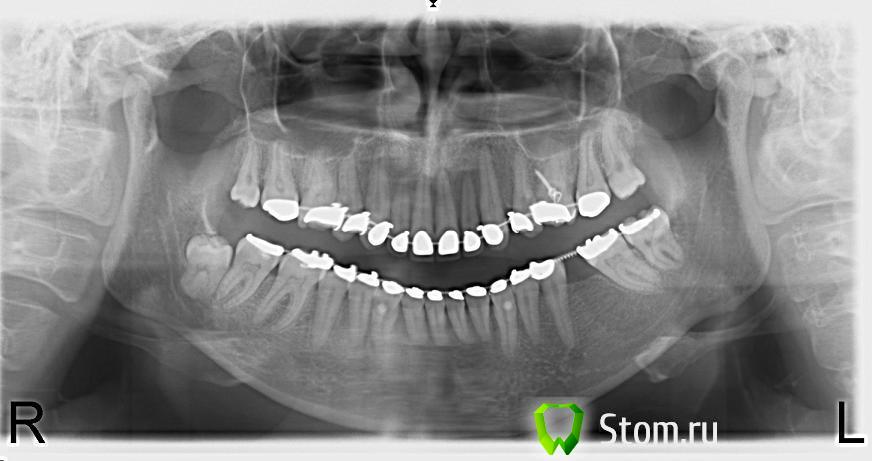

Anna_M Опубликовано 25 января, 2012 Поделиться Опубликовано 25 января, 2012 (изменено) Здравствуйте, уважаемые специалисты! Очень нуждаюсь в вашей помощи и подсказке. Болит 46 зуб. Предыстория: зуб был пролечен и запломбирован по поводу кариеса лет 15 назад. С тех пор не беспокоил. В 2005 году была установлена брекет-система с кольцами на 6-ках. Через год, в 2006, кольцо на 46 расцементировалось, стало болтаться, с этого момента зуб просто адски разболелся, стал сильно реагировать на многие раздражители: холодное, горячее, сладкое, когда кольцо шевелилось, тоже было больно. В общем, пошла лечить. Зуб запломбировали. Кольцо приклеили заново. Боль значительно уменьшилась, от всех ощущений осталась только реакция на холодное. Врач сказал, что зуб пролечен нормально и в этой остаточной реакции нет ничего страшного.С тех пор реакция на холодное так и не прошла. Она то появлялась, то исчезала, в большей или меньшей степени. В принципе, было терпимо. В 2010 г. с наступлением зимних холодов 46 зуб внезапно проснулся, стал очень сильно реагировать на холод, даже если просто выйти на улицу. После воздействия холода долго ныл, буквально часами. Плюс стал ныть и просто к ночи. Конечно же, я пошла к врачу. Сделав снимок, терапевт принял решение зуб не трогать, т.к. «зуб замечательный, пломба тоже». После этого я задала вопрос об этом зубе здесь на форуме. Мне подсказали, что, возможно, судя по снимку, во время того пломбирования в 2006 г. был вскрыт рог пульпы, и мне нужно искать хорошего эндодонтиста. В нашем городе найти его было очень непросто. Пока я занималась поисками, холода прошли, зуб успокоился, осталась малоприметная реакция на холод, но я настолько к ней привыкла, что уж и не обращала внимания. Тем временем была повторно установлена брекет-система, на этот раз лингвальная. Прошел год, снова наступили холода, и снова этот зуб активизировался. Стал ужасно реагировать на холод, долго-долго после этого ныть, периодически побаливал к ночи, из новых ощущений добавились кратковременные несильные «прострелы» (не знаю, как назвать их по-другому). К этому времени я нашла очень сильного эндодонтиста с хорошими рекомендациями и с микроскопом. Итак, в ноябре 2011 (буквально 2 мес. назад) я пошла к нему на прием. Он сделал свежий снимок, проанализировал, сравнил с предыдущим, сказал, что на двух снимках – свежем и годичной давности - есть небольшое расширение в периапексе, но, вероятно, это связано с ортодонтическим лечением, прошлым и нынешним. Никаких изменений в периодонте за год не произошло, динамики нет, из чего следует, что расширение – следствие ортодонтии. Осмотр в кресле выявил реакцию на холодный воздух. Перкуссия безболезненная. ЭОД и холодовой тест эндофростом не проводили. Справедливости ради надо отметить, что рядом стоящие 43, 44 и 45 тоже реагировали на холодный воздух, т.к. на них есть клиновидные дефекты, которые я планирую закрывать после ортодонтии с помощью периопластики. Но я могу четко отдифференцировать реакцию 43-45 на холодовой раздражитель, т.к. она резкая и очень кратковременная, в отличие от реакции 46, которая не так резка, но гораздо более длительна. Чтобы узнать, вскрыт рог пульпы, или нет, доктор решил снять пломбу и рассмотреть все под микроскопом. Сделал два укола анестетика по бокам зуба длинной иглой под углом куда-то глубоко в кость. Сказал, что это хороший метод анестезии, при котором не онемеет пол-лица, а обезболится только зуб… Анестезия совсем не подействовала. Врач сверлил, дул воздухом и поливал водой, как говорится, «наживую». Было очень больно По моему лицу он понял, что больно, доколол еще… Не подействовало. Доктор сказал, что анестетик не дошел до нерва из-за того самого расширения в периодонте. Продолжили так. В итоге, посмотрев под микроскопом, доктор сказал, что никакого намека на вскрытую пульпу тут нет, и закрыл все пломбой. После процедуры сказал, что боль, которую я чувствовала во время лечения, - хороший признак, это значит, зуб живой. С этого момента реакция на холод усилилась. Зуб реагирует уже даже просто на воду комнатной температуры и долго после этого ноет, а если выйти на мороз, то вообще труба. Добавилась неприятная реакция на горячее. Порой эта нудная боль настолько выматывает, что хочется немедленно записаться на прием и депульпировать, наконец, этот многострадальный зуб. Волнует один момент. У меня брекеты инкогнито, которые нельзя переклеивать в силу конструктивных особенностей. Еще во время предыдущего визита доктор сказал ассистенту: «Видишь, тут инкогнито, кламп никак не надеть» и работал, обложив зуб ватками. Если придется делать эндо, то как же быть с коффердамом? И, кроме того, ведь эндодонтист уже осматривал зуб, свой вердикт по нему вынес: пульпита нет, рог не вскрыт, зуб живой, в эндодонтии необходимости нет… В общем, у меня несколько вопросов к вам, дорогие специалисты: 1) что все-таки с 46 зубом: пульпит, или не пульпит? 2) если пульпит, можно ли отложить эндо до снятия брекетов (оно произойдет месяцев через 6-8, ориентировочно). Боль я смогу потерпеть. Мне не впервой, в общем-то. Брекеты приучили к разного рода зубной боли . Главное, чтобы была понятна причина и ясна цель, в этом случае с болью можно смириться. 3) если не пульпит, как избавиться от всех болезненных симптомов и в чем их причина? 4) тот снимок, который сделал врач два месяца назад перед вскрытием пломбы, мне не отдали на руки, поэтому я сегодня сделала в другой клинике свежий прицельный. С этого ракурса стал виден 47 зуб. На нем сверху, на жевательной поверхности, виднеется темное пятнышко, не кариес ли это? И не он ли является причиной всех моих мучений? Может такое быть, что боль от кариеса на 47 иррадиирует в 46 и путает диагностическую картину? Буквально три дня назад с 47-го зуба спилили ортодонтическую накусочную пломбу, которая весь год покрывала всю жевательную поверхность этого зуба и была налеплена поверх обычной терапевтической пломбы, сделанной тоже лет 15 назад. Может ли быть такое, что под этой ортодонтической накладкой развился кариес, который никто не заметил из-за того, что это место было полностью ею закрыто и кариес не визуализировался при осмотре? Прикрепляю снимки: 1. годичной давности 2. свежий сегодняшний 3. на всякий случай прикреплю ОПТГ для полноты картины (орто не слишком свежее, конечно, июль 2011, но хоть что-то). Изменено 25 января, 2012 пользователем Anna_M Ссылка на комментарий

Scrabble Опубликовано 30 апреля, 2012 Поделиться Опубликовано 30 апреля, 2012 17 зуб по орто странно выглядит. Что на нём фиксировано? Нет признаков расцементировки? Сама попробуй сделать пробу с горячей водой-возьми ватный шарик(небольшой, чтобы соседние зубы не задевал), смачивай его в очень горячей воде и прикладывай последовательно к шейкам 17, 46, 47. Почему 48 оставили ортодонты-тоже непонятно. Карман дистально от 47 есть? Ссылка на комментарий